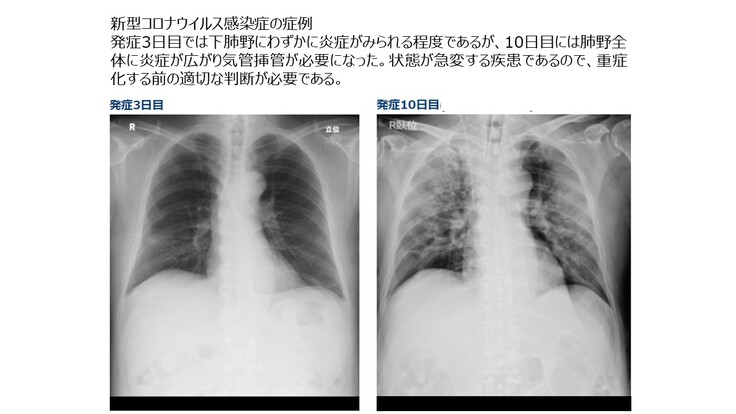

●新型コロナウイルス感染症でも画像診断が重要

新型コロナウイルス感染症の重症化を防ぐためには正確な画像診断が必要です。新型コロナウイルスによる感染はPCR検査で検出できると一般には考えられていますが、PCR検査での検出精度は70%程度と言われており、PCR検査が陰性でも感染している症例は数多く存在します。また正確な診断が間に合わず自宅やホテルでの療養中に死亡する例も多数発生しています。

そこでWHOでは新型コロナウイルス感染症の診断に対して画像診断を利用するようにアドバイスを行っています。(胸部画像診断の COVID-19 への適用:緊急アドバイスガイド)

新型コロナウイルスによる感染拡大が一段落しても、季節性インフルエンザのように人類は新型コロナウイルスと共存することが必要となります。したがってWHOがアドバイスを行っているように入院前に一般のかかりつけ医などが画像診断を行い、専用病棟への入院の必要性などを判断するケースが想定されます。